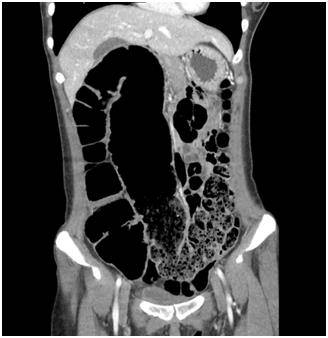

![서행성변비 복부 CT 영상. 상행 결장에서 횡행 결장이 심하게 늘어나 있으며 이보다 항문에 가까운 쪽에 대변이 차 있다. 대장 내 종괴 등 폐쇄를 유발하는 원인 병변은 보이지 않는다. [서울대병원 제공]](https://img2.daumcdn.net/thumb/R658x0.q70/?fname=https://t1.daumcdn.net/news/201905/15/yonhap/20190515070012871ycxl.jpg)